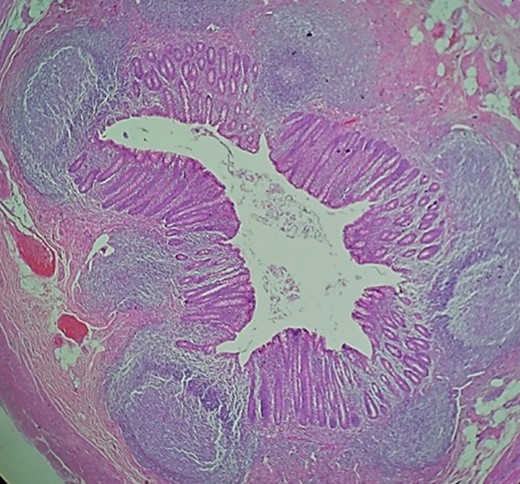

Pathology, appendix wall with acute mucosal inflammation and neutrophilic infiltrates in its wall.